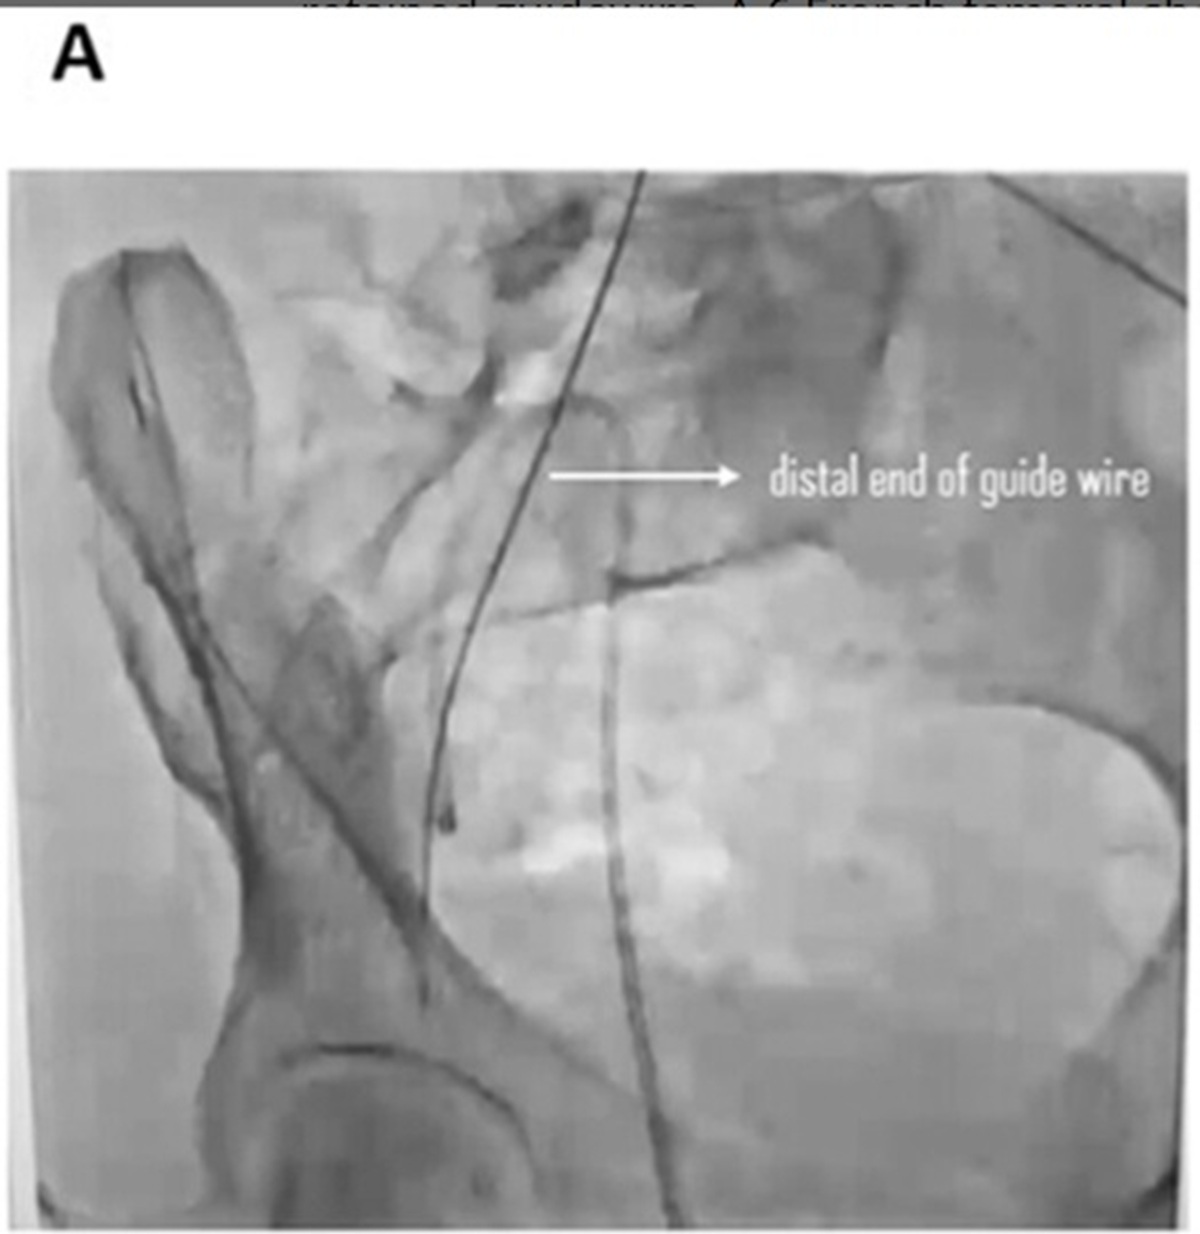

• A 50 cm guidewire was accidentally left inside her during a hospital procedure.

• The guidewire was intended to help place a catheter and should have been removed after the procedure.

• The woman remained symptom-free for three months until an X-ray revealed the wire.